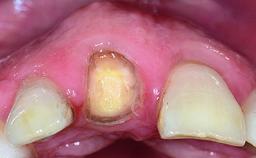

A 28-year-old patient presented at her general dentist’s office and complained about the appearance of her tooth 21. The patient had a history of trauma to this tooth. Endodontic treatment had been performed in the past and a crown placed on the tooth. A procedure to replace the old crown was performed by her dentist; however, a perforation on the middle third of the root occurred, and extraction of tooth 21 was suggested. Upon clinical and radiographic examination of the patient, who had been referred to us, replacement of tooth 21 by a dental implant appeared to be indicated.

Bone Volume Deficient horizontally, allowing simultaneous augumentation